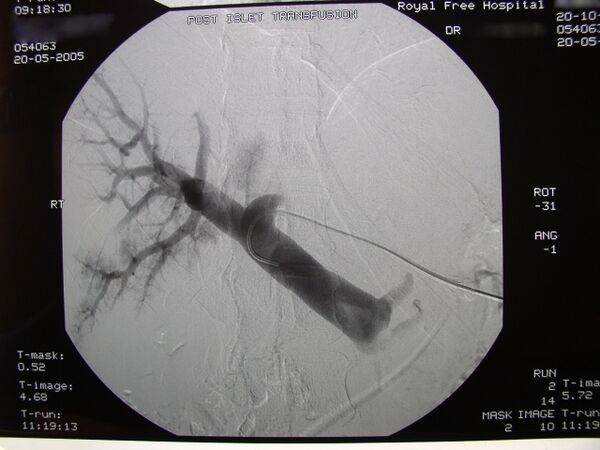

Под местной анестезией реципиенту вводят катетер в воротную вену печени под контролем ультразвуковых и рентгеноскопических методов визуализации. Таким образом, донорские панкреатические островки по катетеру вводятся в воротную вену печени. В случае противопоказаний для проведения местной анестезии, хирург осуществляет пересадку панкреатических островков под наркозом через небольшой разрез. Среди возможных рисков оперативного вмешательства кровотечение или образование тромбов.